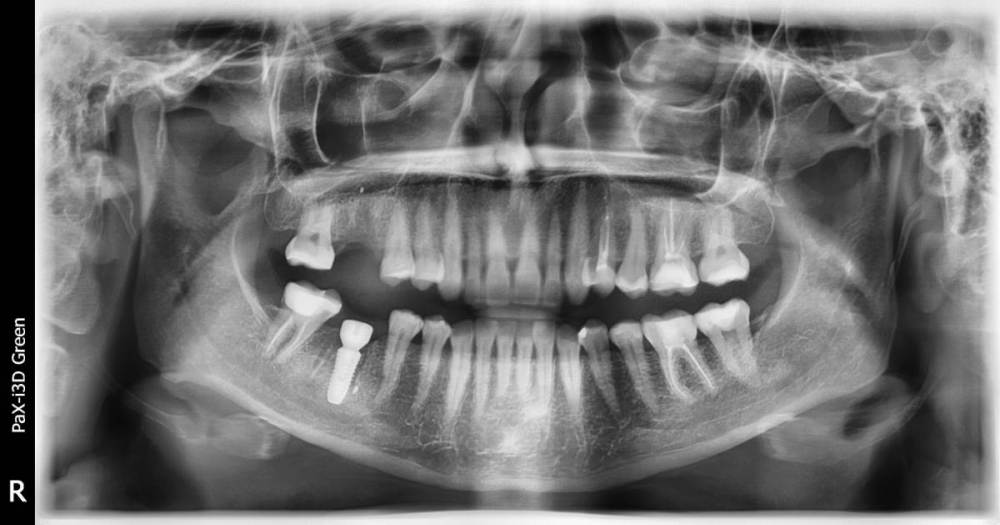

Добрый день! На верхушке корня 26 зуба была обнаружена гранулема.  Проведена ревизия каналов, временное пломбирование пастой каласепт, через две недели постоянное гуттаперчевыми штифтами. Постпломбировочные боли вторую неделю довольно сильные. Есть ли шанс спасти зуб?

До лечения

2 (1).jpg